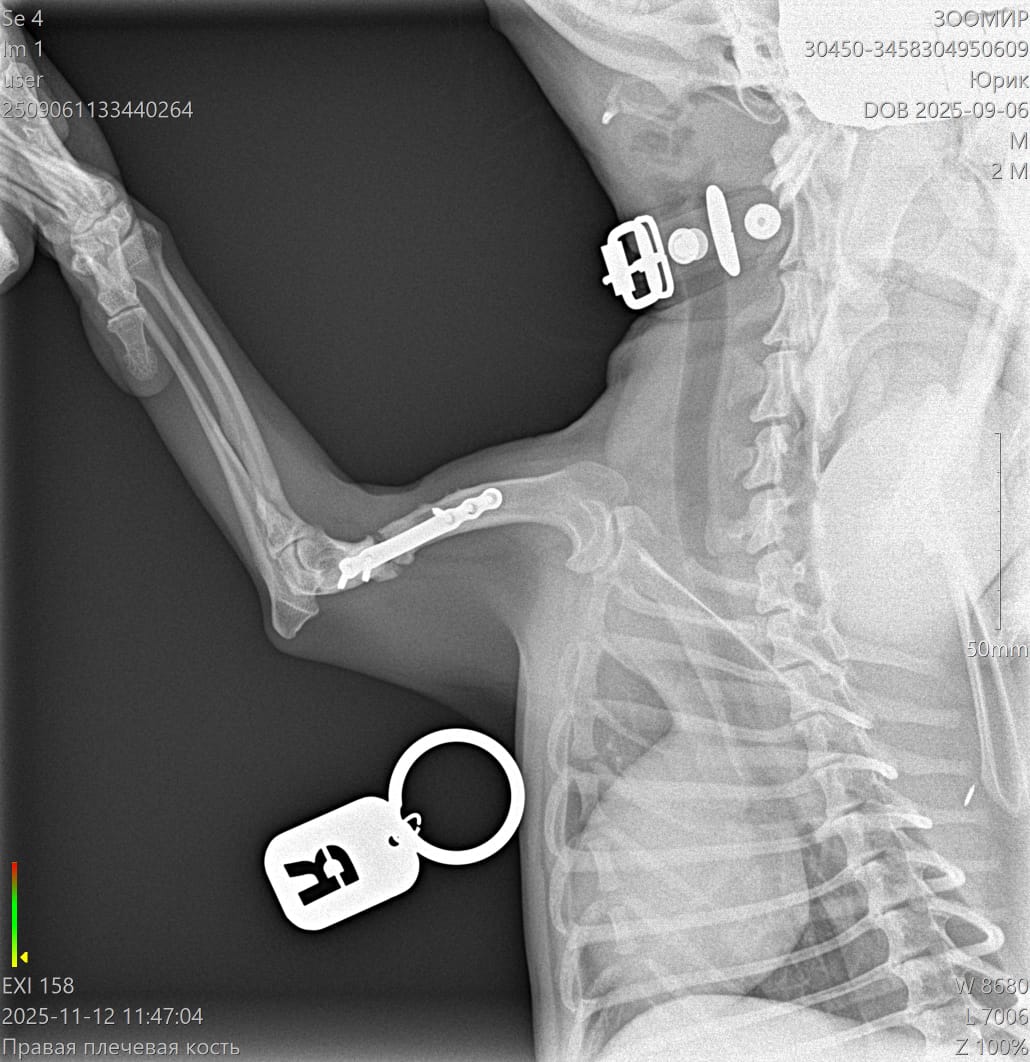

Сделали контрольный рентген - пока мозоли не видно:((((

Лапой на ровном немного пользуется. Но это за счет пластины.

Рентген

Юрик съездил сегодня на контрольный рентген.

Мозоль ОБРАЗОВАЛАСЬ. По центру она еще не очень плотная, но кость срослась.

Как Ольга паразита не оберегала, но на рентгене оказалась чуть погнутая пластина и один сломанный винт.

Снимать ничего не будем из конструкции, если не начнет отторгаться или двигаться.

2 рентгена и осмотр АН обошлись в 2600₽ ( это стоимось 2 снимков).

Юрик. Взгляд изнутри